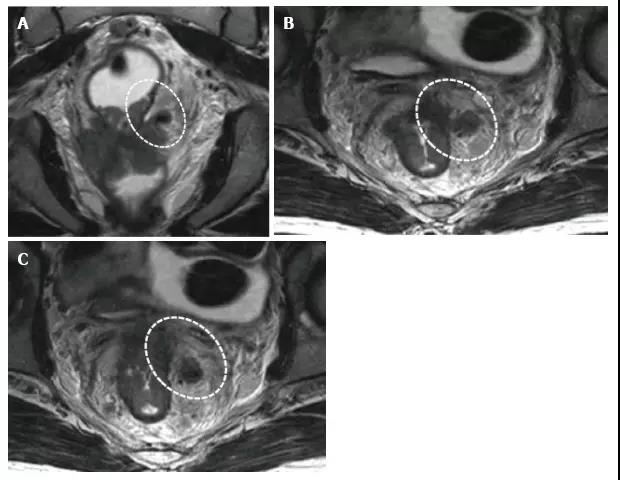

在 T2 加权(A)冠状面(B,C)轴向磁共振图像显示,直肠癌浸润提肌(红色箭头)和直肠系膜筋膜(白色箭头)。LA:肛提肌;PR:耻骨直肠肌;MRF:直肠系膜筋膜;BL:膀胱;V:阴道。